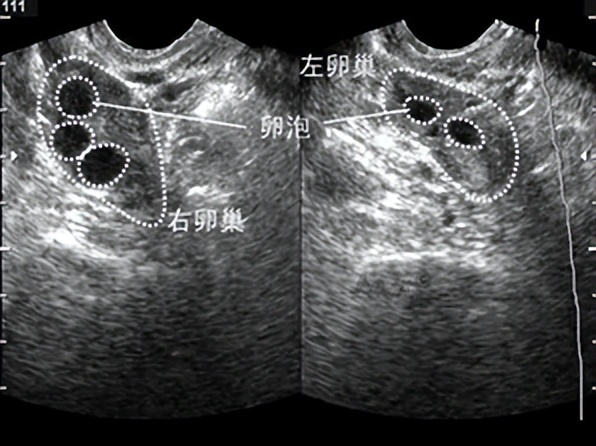

卵泡的生长周期:窦卵泡(月经期):卵巢内多个直径<10mm的小卵泡。

生长卵泡(月经周期10天左右):

卵泡直径生长到10mm以上,一般有1-2个。

优势卵泡(月经周期12天左右):

卵泡直径达到15mm及以上,一般只有1个。